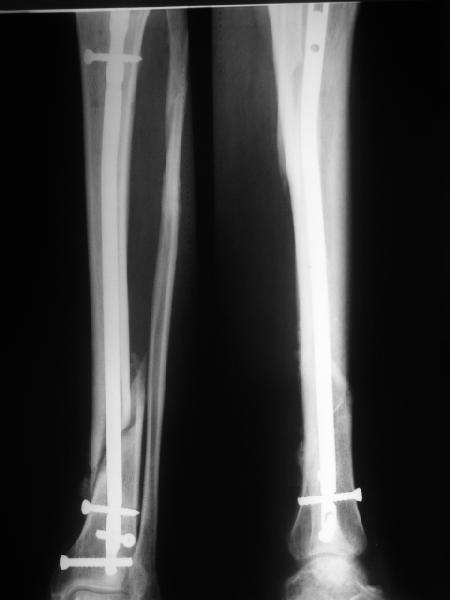

КА> Но почему решение динамизировать на сроке 8 недель с полным

В приложении картинка пациента со сломанным внизу гвоздем. Начал лечение в другом учреждении. Еще и адвокат к тому же.

Динамизировали через 8 недель, а оно поползло больше, чем хотелось бы.